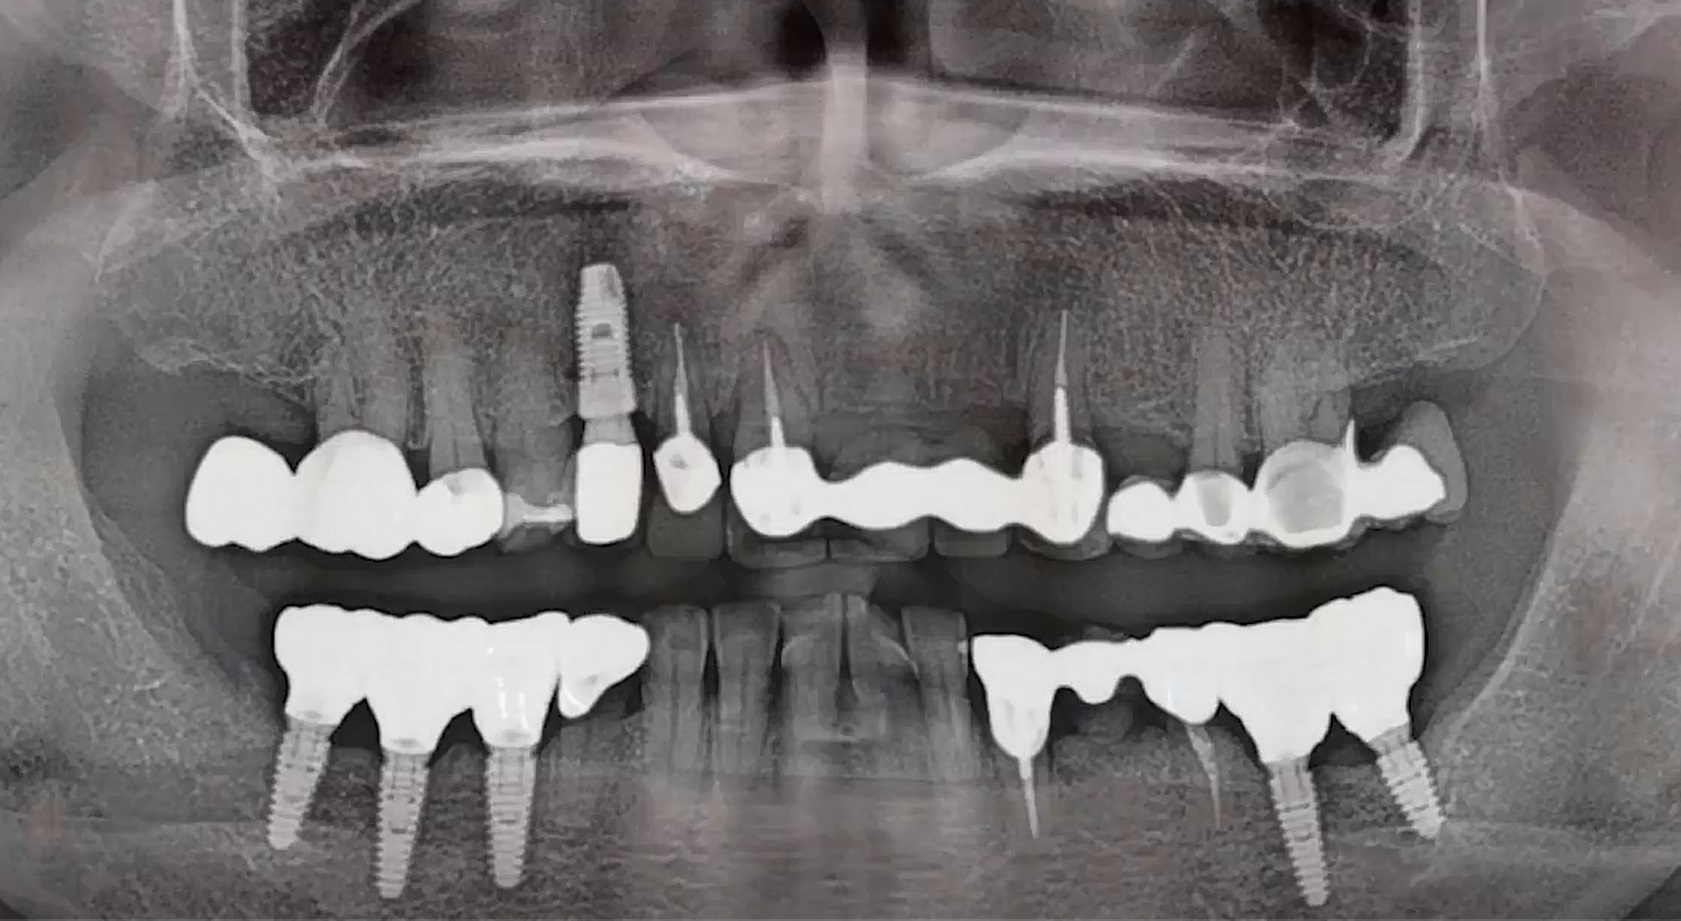

Dr. Hyung Jun Kim,Edentulous,Maxillary Anterior,Maxillary Posterior,Mandibular Anterior,Mandibular Posterior,#12,#22,#32,#45,#14,#24,#36,#46,#15,#25,#37,#47,#17,#27,#41,Immediate Placement,AnyRidge,Full-mouth implants,Full mouth rehabilitation,Octa abutment,Long-term clinical case,Biological stability